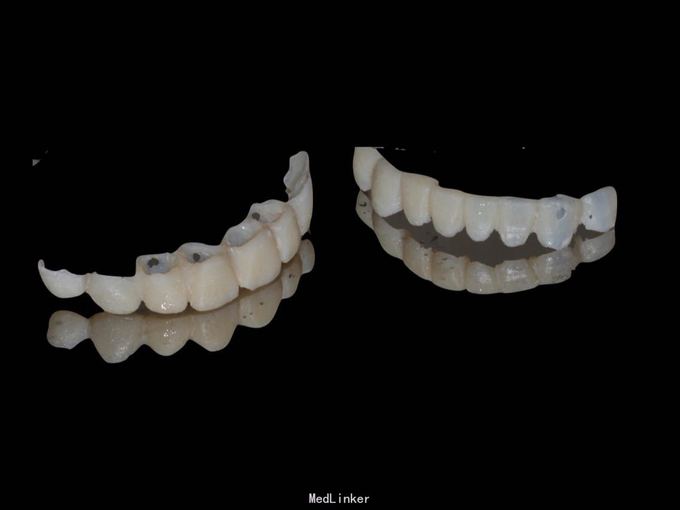

11 12 21 22死髓牙,不良修复体,牙龈炎 36 37 46 47残根 牙列不齐 处置:全口洁治。 比色,拍照,取模型做蜡型。 拆除旧修复体,拆桩核,做根管治疗,纤维桩修复,牙体预备,取模,做临时冠,粘固。11 12 21 22全瓷冠修复,13 14 23 24 31 32 33 34 41 42 43 44瓷贴面修复。